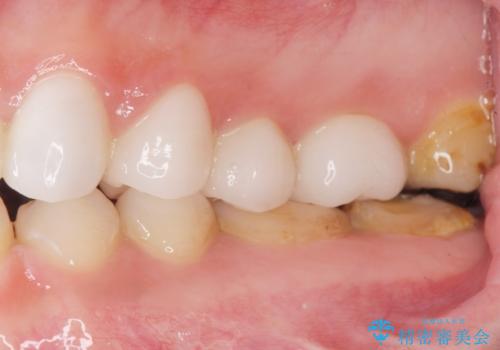

綺麗な仕上がりにご満足下さいました。

奥歯の咬み合わせも良くなったと喜んで頂けました。

患者様の理想とする韓流アイドルの写真を技工士さんに送り、最終的なクラウンの形や色をできるだけ理想に近づけられるよう努めました。

下顎はホワイトニングを行っております。

クラウンの種類:オールセラミッククラウン スタンダード